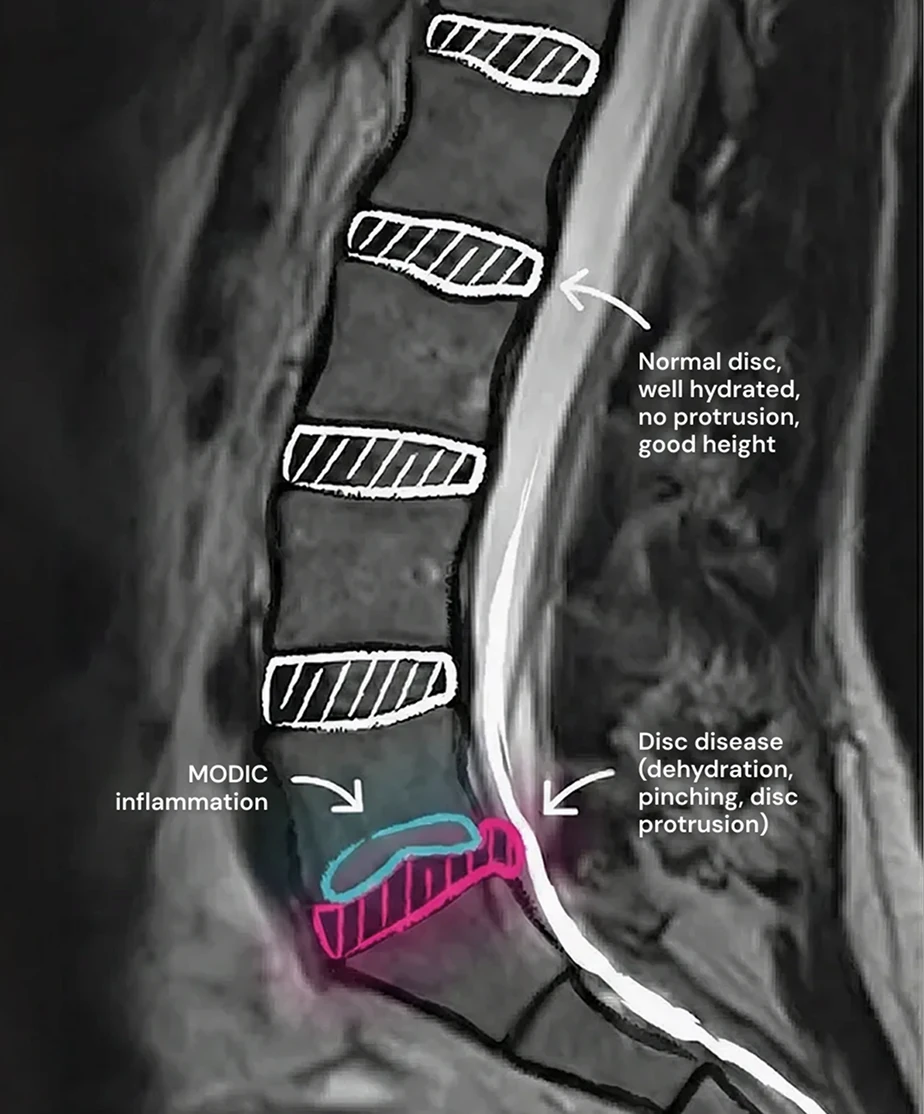

Annotated lumbar spine MRI showing a herniated disc with dehydration and protrusion compressing spinal nerves, compared with normal healthy discs.

In cases of significant herniation, the disc (or disc fragments) can compress spinal nerves, resulting in chronic sciatica in one or both legs and the gluteal region. The disc itself may also become dehydrated, bulging (protrusion), and sometimes inflamed, causing pain without direct nerve compression.